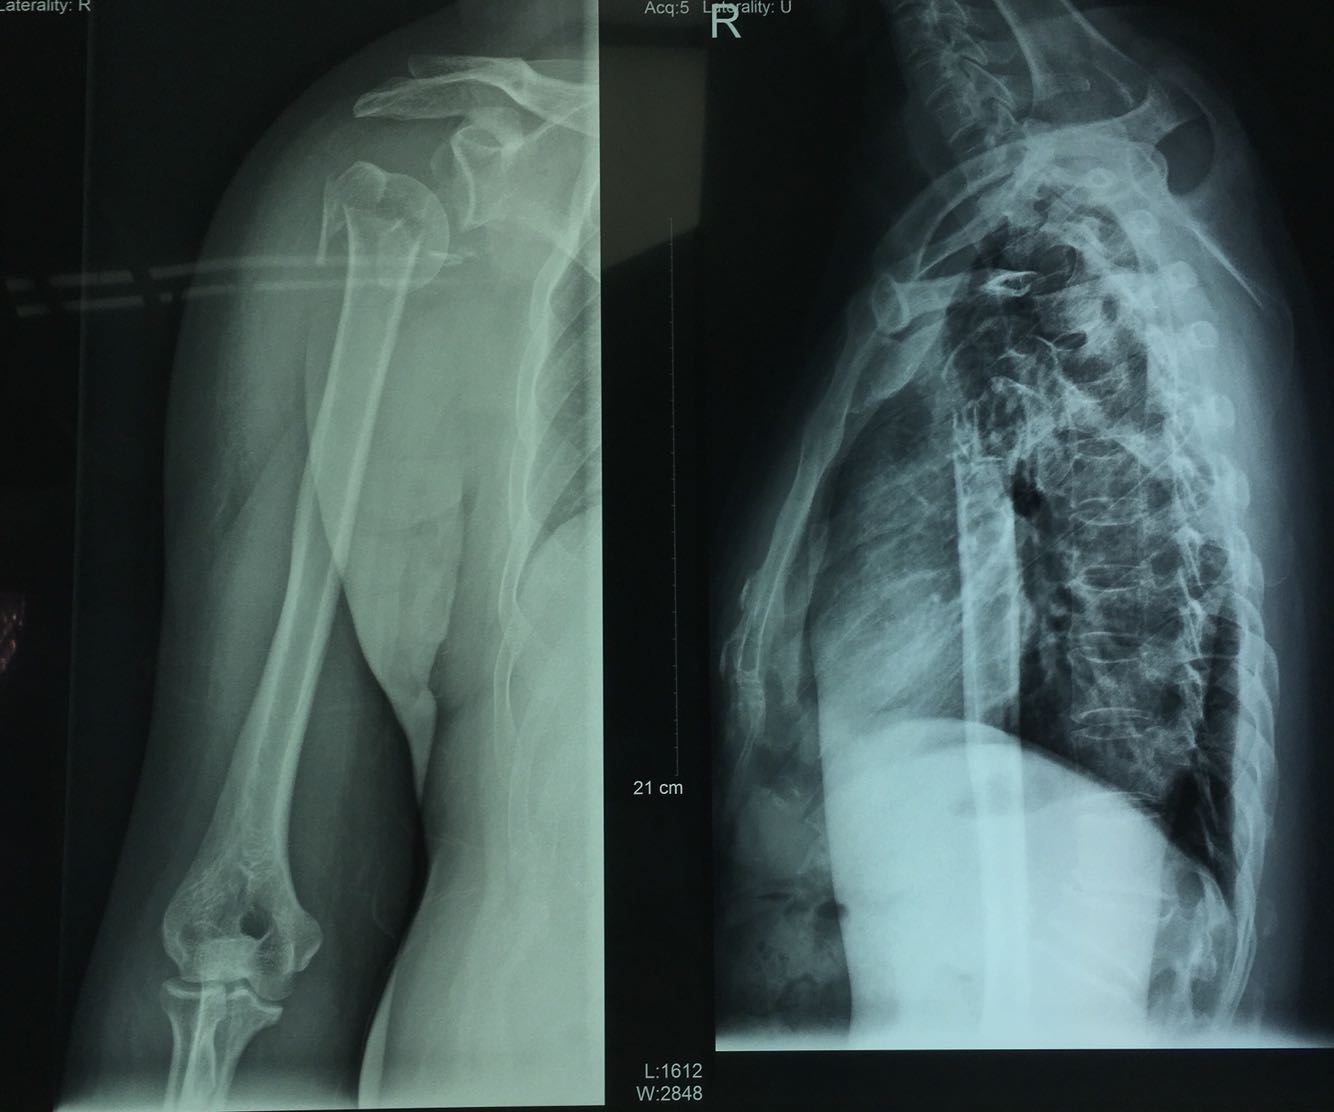

查体:体温36.6℃,脉搏93次/分,呼吸20次/分,血压118/69mmHg,体重71kg。神清,右臂绷带悬吊,解除绷带后,可见右肩部肿胀,局部压痛,纵向叩击痛(+),右肩部、上臂近端畸形,可闻及骨擦音。右肱骨上段皮肤张力稍高,皮温略高,少量片状紫斑,未见水泡,被动牵拉痛(+)。右肩关节、肘关节因惧怕疼痛不敢活动,右腕关节活动正常,右手各指活动正常,感觉功能良好,桡动脉波动可扪及,末梢血运良好,甲床毛细血管反应良好。 辅助检查:血常规:RBC 2.83×10^12/,HGB87g/L;凝血四项:Fbg C3.51g/LL,D-DimerDimer 7.54mgmg/L FE;肝肾功:DBIL 138mol/L,IBIL 17.7umol/L,TBIL 31.5umol/L;余无异常。 影像学检查: 骨骼系统x线片:1.右肱骨颈骨折并右肩关节脱位,2.胸部x线片未见异常,3.腰1椎体压缩性骨折 四肢CT平扫:右盂肱关节正常解剖结构消失,右肱骨近端骨质断裂,连续性中断,见多发透亮显影,周围见游离骨碎片影;;右肱骨头向外下移位,断端肱骨干向内上移位,嵌插于右肱骨头部。关节囊周围软组织肿胀明显,肌肉间脂肪界限模糊。三维重建所见同平扫。右侧肱骨近端粉碎性骨折并右肩关节脱位,断端错位。 心电图无明显异常。

诊断:右肱骨近端骨折 治疗:臂丛备全麻下行右肱骨近端骨折切开复位内固定术,手术过程顺利,麻醉完全,骨折部位复位良好。